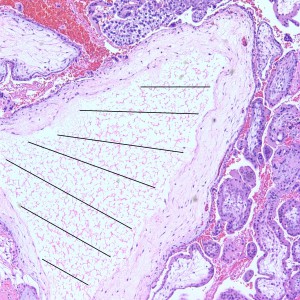

Some villi are so large and hydropic that a few have actually developed central cisterns, spaces within the center of the villi (space highlighted by horizontal lines).